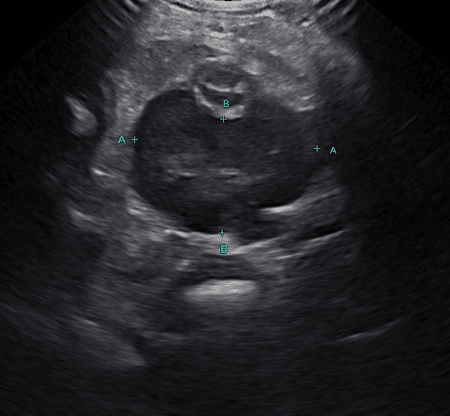

Small intestinal abnormalities on ultrasound can be broken into two main categories: focal and diffuse disease. Focal small intestinal lesions include mechanical obstruction caused by foreign material, intussusception, or a mass. Masses are described as circumferential, asymmetrically circumferential, or eccentric (Figures 1a-1c). In dogs, one study noted that 99% of dogs with intestinal neoplasia have a loss of wall layering; unfortunately, there can be some overlap between benign and malignant masses on ultrasound. The more common intestinal mass neoplasms include adenocarcinoma, lymphoma, gastrointestinal stromal tumor, leiomyosarcoma, leiomyoma, and mast cell tumor. In cats, the most common intestinal masses are lymphoma or adenocarcinoma, followed by mast cell tumors. Lymphoma can present as solitary or multiple masses or a diffuse altered wall layering. Carcinomas most often are transmural lesions with loss of wall layering and can result in the narrowing of the lumen and secondary mechanical ileus. Mast cell tumors most commonly present as a focal mass that is hypoechoic and either eccentric or asymmetrically circumferential, similar to other intestinal neoplasms, and is rarely reported as a diffuse intestinal wall thickening. An interesting point documented in cats is that mast cell tumors in the intestine can often alter but not completely disrupt the wall layering. In dogs, it has been reported that there are no ultrasonographic signs to help differentiate between gastrointestinal spindle cell tumor types as they most often are seen as eccentric and bulging out of the serosa; however, gastrointestinal stromal tumors were more commonly seen in the cecum and large intestine.

Figure 1b (above): Example of a circumferential small intestinal mural mass diagnosed as lymphoma.

Figure 1c (above): Example of an asymmetric, circumferential small intestinal mural mass diagnosed as lymphoma.